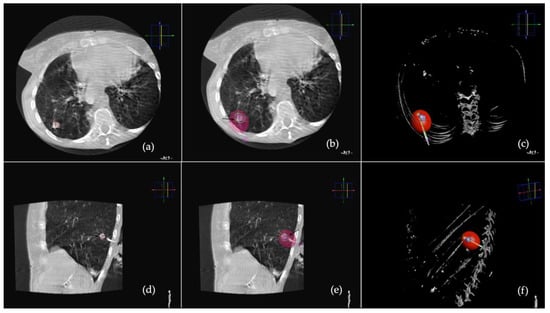

- Ierardi, A.M.; Petrillo, M.; Xhepa, G.; Laganà, D.; Piacentino, F.; Floridi, C.; Duka, E.; Fugazzola, C.; Carrafiello, G. Cone Beam Computed Tomography Images Fusion in Predicting Lung Ablation Volumes: A Feasibility Study. Acta Radiol. 2016, 57, 188–196. [Google Scholar] [CrossRef]